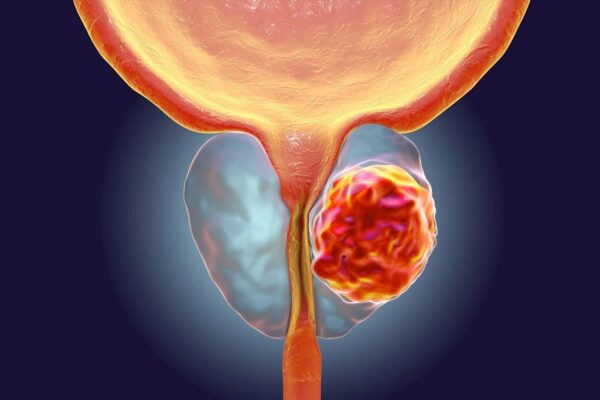

El cáncer de próstata es la neoplasia no cutánea más común. Diversos estudios de autopsias han revelado que más del 40% de los hombres mayores de 50 años presentan algún tipo de cáncer prostático, y esta prevalencia aumenta con la edad. Se estima que el 30% de los hombres de entre 60 y 69 años y el 67% de los hombres de 80 a 89 años tienen evidencia de cáncer prostático en sus órganos tras la autopsia.

El cáncer de próstata se caracteriza por una notable heterogeneidad biológica, lo que significa que no todas las formas de la enfermedad son iguales ni tienen el mismo comportamiento. La mayoría de estos cánceres ocultos, es decir, aquellos que no presentan síntomas clínicos evidentes, son de pequeña dimensión, de crecimiento lento (indolentes) y se encuentran confinados al órgano sin mostrar signos de propagación a otras áreas del cuerpo, como los ganglios linfáticos o tejidos distantes (metástasis). Esto sugiere que una porción significativa de estos casos no pone en peligro la vida del paciente, dado su carácter indolente y limitado al órgano afectado.

A nivel mundial, el cáncer de próstata ocupa el segundo lugar en cuanto a frecuencia de aparición de malignidades en hombres, y es la quinta causa principal de mortalidad por cáncer. Estos datos reflejan la carga considerable que representa esta enfermedad tanto a nivel individual como poblacional, especialmente considerando que una porción significativa de estos casos son asintomáticos y detectados solo a través de autopsias. Además, los enfoques diagnósticos y las estrategias terapéuticas continúan evolucionando, en parte debido a la disparidad entre la alta prevalencia subclínica y la incidencia clínica que desencadena la mortalidad. La naturaleza heterogénea del cáncer de próstata y la posibilidad de que muchos casos permanezcan no diagnosticados o clínicamente irrelevantes desafían el tratamiento y manejo de la enfermedad, lo que obliga a una evaluación cuidadosa de cada caso individual.